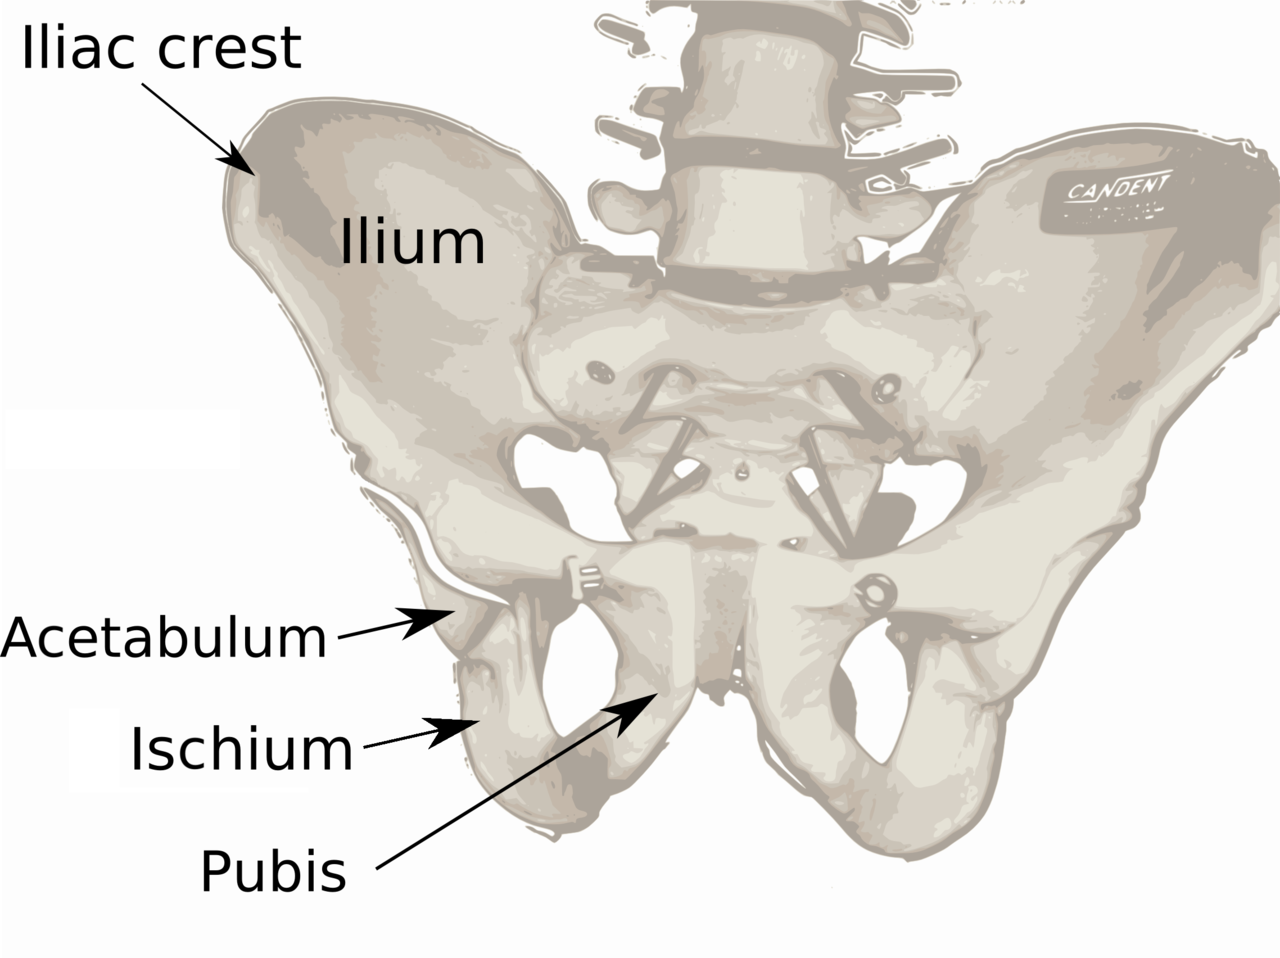

When faced with a challenging clue like “pelvic bones,” it’s essential to think outside the box. Consider related terms such as anatomy, skeletal system, or even medical terminology. Sometimes, the answer lies in a different context than you initially thought.

Another approach is to break down the clue into its individual parts. In this case, “pelvic” refers to the area of the body, while “bones” obviously points to skeletal structures. By dissecting the clue in this manner, you may uncover hidden connections that lead you to the correct answer.

Ilium bone Wikipedia